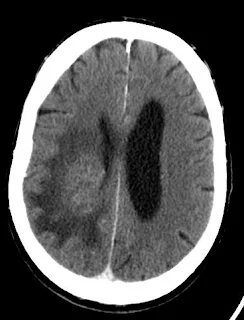

5.glioma

Glioma adalah kanker susunan syaraf di susunan saraf pusat (otak).